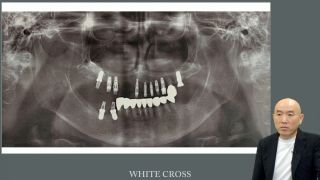

クリニカル・パールとは、経験豊富な臨床医が見つけ出した一般化された原則、いいかえれば「先人の教え」である。インプラント治療は若手歯科医師に人気が高い反面、修得には長い経験を要する。約20年間、1300名を超える臨床研修歯科医を指導してきた私が得たインプラント治療のクリニカル・パールについて、症例を通じてお伝えする。これからインプラント治療をマスターしたい若手の先生にとって臨床のヒントとなれば幸いである。